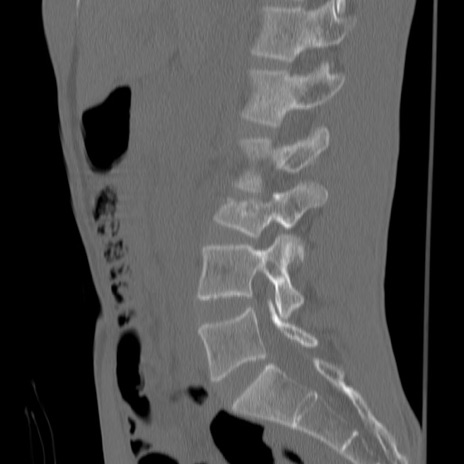

症例3 腰椎CT(矢状断像)

【症例】30歳代男性

【主訴】腰痛

【現病歴】本日旅行先で観光中に、友人と衝突し転倒し受傷。

【身体所見】麻痺なし、右下腿内側前面外側、左下腿内側に知覚鈍麻・しびれ

異常所見と診断は?

腰椎CT

3D再構成